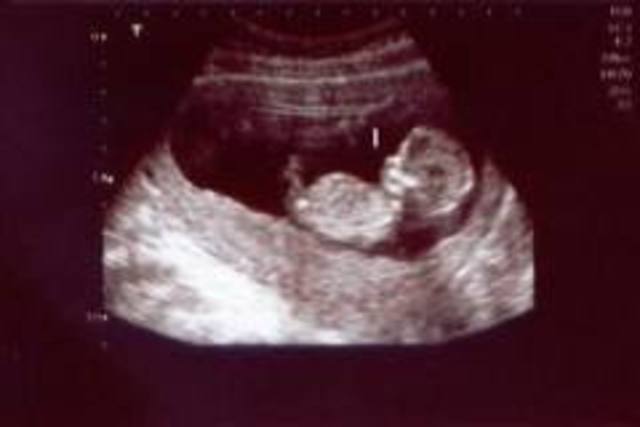

2d ultrasound3